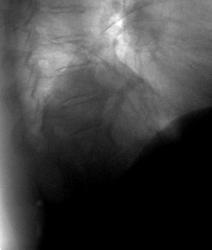

Пациентка предъявляет жалобы только на прогрессирующую потерю зрения.... Выявлена при профилактическом исследовании - окончательного мнения нет, наблюдается в динамике....

периферическая опухоль н/доли левого легкого. Учитывая жалобы, сделайте КТ (МРТ) головного мозга для исключения мтс

На мой взгляд, на настоящее время, имеет место только ателектаз нижней доли и некоторое увеличение язычкового сегмента в объёме.

На всех боковых рентгенограммах виден плавный переход контуров нисходящей аорты в "загадочное" образование - это случайное скиалогическое явление или все - таки аневризма? А образование пульсирует?

А почему на прямой рентгенограмме не виден плавный переход контуров нисходящей аорты в образование, и основная масса образования далековато о аорты7

Валентин Львович, когда периферический узел уже подрастает к корню, т.н. "централизация", нарушается бронхиальная проходимость и может развиваться гиповентиляция и ателектаз. А увеличение объема Вы наверное имели в виду в язычковых сегментах?

Нижняя доля спадается – нет сомнений. Но крупная опухоль периферического бронха должна быть видна отчётливей. И хотелось бы увидеть изображение крупных бронхов, полученное тем или иным способом.

Я так полагаю, ателектаз нижней доли. Делайте ТМГ и отправляете в онколдиспансер. Тут вероятнее центральный рак нижнедолевого бронха

Сегодня, после 8 месяцев, пришла ко мне вышеописанная пациентка. Я был удивлен и очень рад! Была она у родственников (детей) в Питере. Сделали ей операцию. Немного похудела, но чувствует хорошо. Резудьтат гистологии - лейомиома! А наши онкологи - не решились. Вот такой финал!

Лейомиома легких - редкий (за время работы - 2-3 случая встречались) случай. Заключение гистологии НИИ онкологии им. Петрова Н.Н.: Веретеноклеточная опухоль со значительным количеством межуточного вещества. Лейомиома. Клетчатка без метастазов. Целесообразно ИГХ (?).

Лейомиома относится к числу редких доброкачественных опухолей легких, развивающихся из гладкомышечных волокон, входящих в состав стенки бронха или кровеносных сосудов. Она имеет хорошо выраженную капсулу. Центральные опухоли имеют вид полипа на ножке или широком основании, иногда наблюдается и перибронхиальный рост. Периферические опухоли могут быть в виде множественных узлов. На разрезе ткань опухоли розоватого цвета, поверхность зернистая, со спиралеобразной волокнистостью. В соединительно-тканной

строме выявляются псевдожелезистые структуры и кистевидные образования.